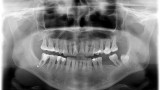

Bogata w płytki i leukocyty fibryna jest stosowana w regeneracji tkanek od ponad 15 lat. Pozytywny wpływ PRF (platelet-rich fibrin) na regenerację tkanek miękkich jest niewątpliwy, bezsporny i częściowo udowodniony w badaniach klinicznych i analizach biochemicznych. Wpływ PRF na regenerację tkanki kostnej jest obserwowany klinicznie, ale nadal niedostatecznie poznany jest mechanizm tego zjawiska.

Platelet- and leukocyte-rich-fibrin has been used in regeneration of tissue for more than 15 years. The positive influence of PRF on the regeneration of soft tissue is undoubtedly, without question and partially proven in clinical studies and biochemical analysis. Influence of PRF on regeneration of bone tissue is observed clinically but the mechanism of this phenomenon is still not sufficiently known.